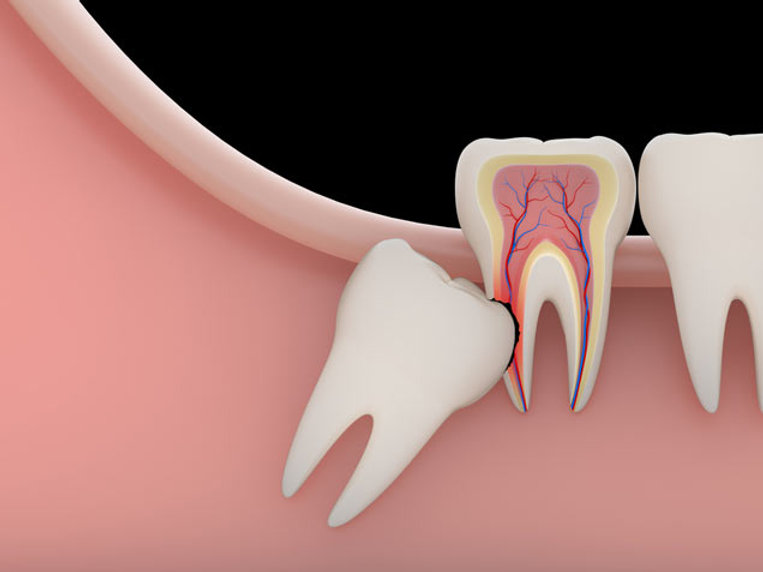

The modern human jaw is simply too small to comfortably accommodate a third set of molars in most people. This mismatch between tooth size and jaw size is the root of most wisdom tooth problems.

When there is not enough room for the tooth to erupt fully and in the correct position, it becomes impacted. An impacted wisdom tooth may grow sideways, at an angle, or remain completely buried beneath the gum.

| Mesial | Tooth angles forward toward the front of the mouth |

| Distal | Tooth angles backward toward the back of the mouth |

| Vertical | Tooth faces the right direction but cannot fully erupt |

| Horizontal | Tooth lies completely on its side |

Each type of impaction carries its own set of risks and complications. Some can damage neighboring teeth, while others create pockets where bacteria thrive.